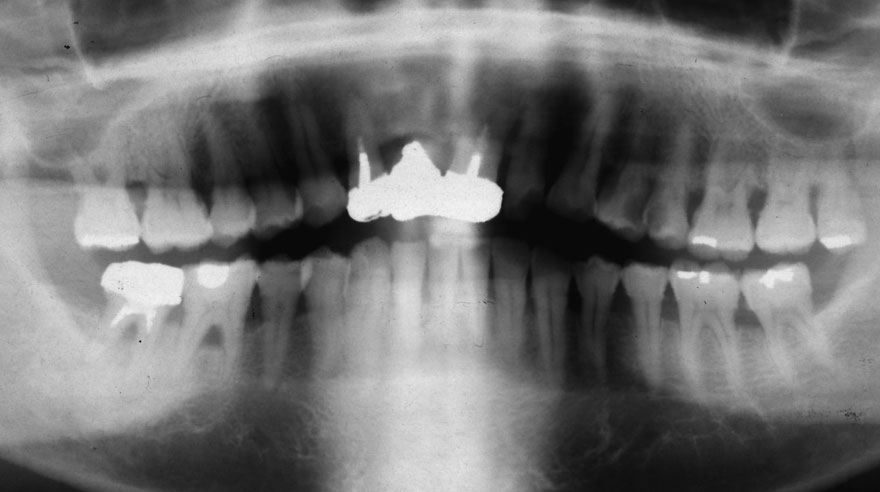

初診時 40歳 女性 平均歯槽骨喪失量:5.24mm

20年後 60歳

平均歯槽骨喪失量:5.79mm

21年間喪失量:-0.55mm

年間喪失速度:-0.027mm

(ケア頻度:1.23ヵ月ごと)